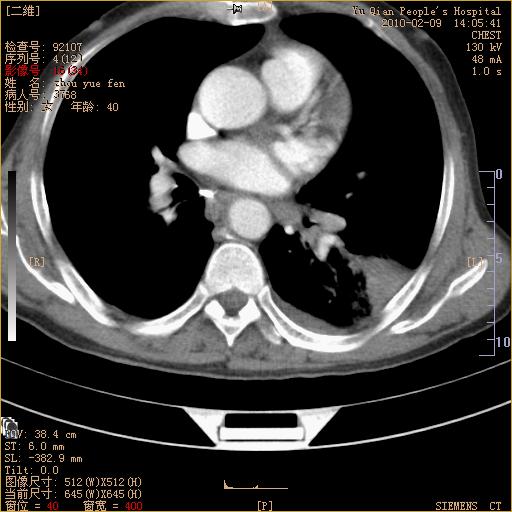

男性,73岁,咳嗽咳血数天,诊为肺ca伴左肺下叶后段阻塞性炎症、肺不张妥否?

右下肺有转移?

左下肺中央型肺癌伴结段形肺不张,左侧胸腔积液,纵隔内见部分增大淋巴结(反应性增生或转移)

左下基底干支气管明显变窄。

左肺下叶基底段支气管狭窄,左肺门增大,左肺下叶团片状病灶。中心型肺癌伴柱塞性炎症可能大,建议支气管镜检查。

左下肺中央型肺癌伴节段性肺不张,左侧胸腔积液,纵隔内见肿大淋巴结

左下基底段支气管变窄。建议进一步纤支镜检查。

1、左肺下叶后基地段肺癌伴阻塞性炎症,左下肺门淋巴结转移。2、左侧胸腔积液。